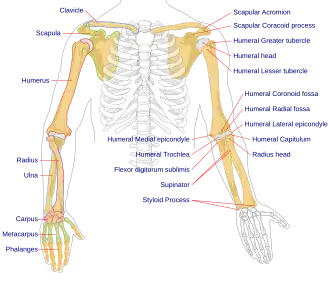

Anatomy - Biological engineering